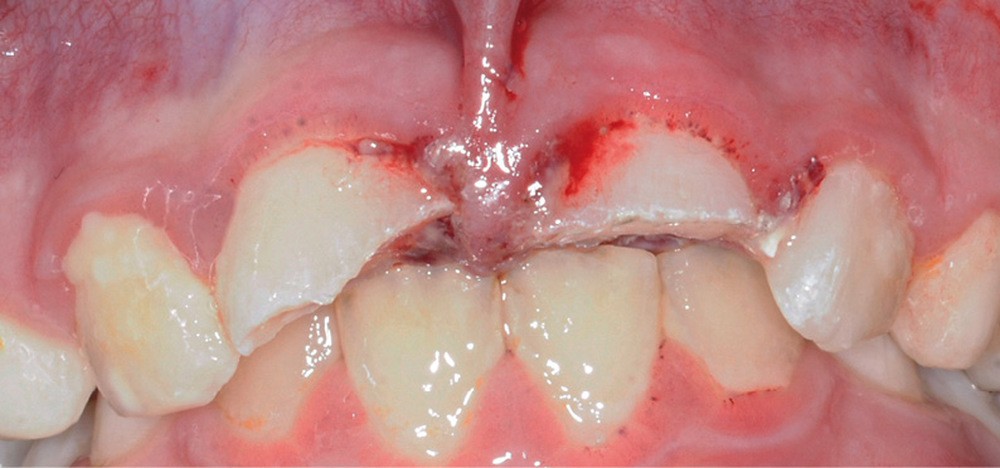

Tous ces examens se révèlent négatifs. Nous procédons donc à l’examen de la sphère orale qui objective :

- une plaie au niveau du frein labial supérieur ;

- une fracture corono-radiculaire avec effraction pulpaire de 11 et 21 (fig. 1 et 2) ;

- une subluxation de 11 et 21 (saignements sulculaires).